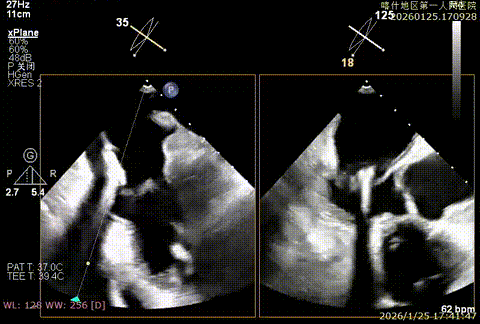

X-plan重度反流

3D enface后叶栓系

3D enface观察反流

该例患者为VFMR,术前制定手术策略:患者二尖瓣重度反流,后叶严重栓系,心房心室扩大。患者瓣口面积4.5cm2,预计使用两枚XTR解决患者瓣叶脱垂和反流。考虑到先于2区进行钳夹,应该能获得足够的房间隔穿刺高度。术中经不断调整穿刺位点,最终穿刺高度4.4cm。成功穿刺后将第一枚XTR送入二尖瓣正上方,进行弹道测试Orientation调整后,最终定位于2区正上方下左心室。第一枚夹子在左室成功捕捞和钳夹瓣叶后,瓣叶反流程度显著降低,夹子外侧仍见部分反流,随后在第一枚夹子外侧再次放置一枚XTR,瓣叶反流程度进一步降低至微量。通过TEE观察,二尖瓣双孔组织桥稳定,跨瓣压差3mmHg,肺静脉逆流改善明显,手术安全结束。